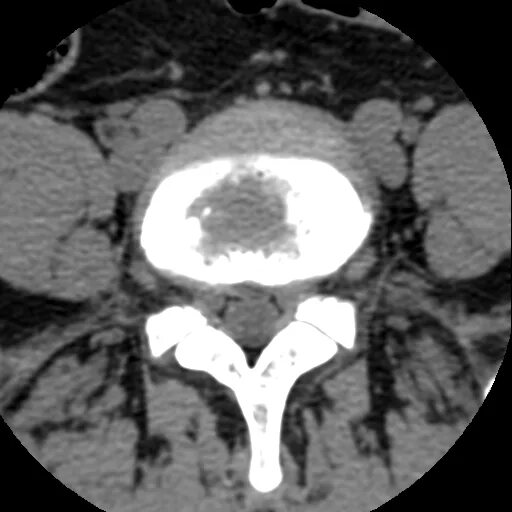

Грыжи на кт